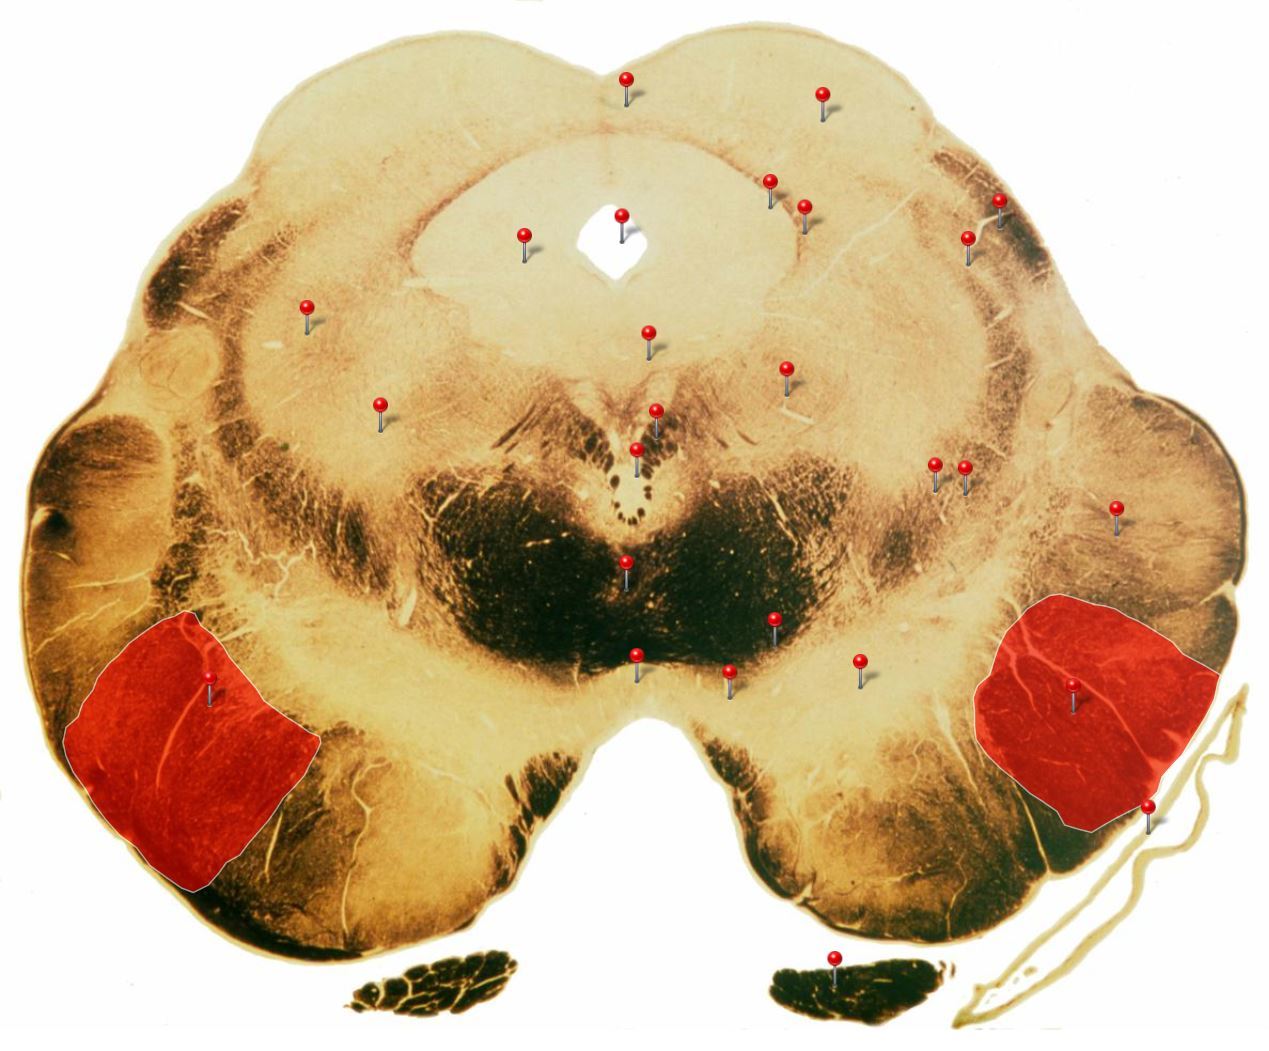

Corticospinal Tract

Rostral Medulla

Controls precision and speed of skilled movements involving the distal muscles of the contralateral limbs, particularly those of the hands and fingers

Nucleus Ambiguus

Neurons supply the muscles of the pharynx, larynx, upper oesophagus and heart

Basilar Artery

Provides blood supply to much of the cerebellum, pons, midbrain and posterior thalamus as well as part of the temporal (inferior surface) and occipital (medial and inferior surfaces) lobes

Olives

Elevations formed by the inferior olivary nuclei which integrate information from a variety of sources before relaying it to the cerebellum

Rubrospinal Tract

Assists in the control of movements of the hands and fingers

Medial Vestibular Nucleus

Process inputs from vestibular receptors of the inner ear and are involved in the regulation of posture and the coordination of head and eye movements

Spinal Trigeminal Tract

Transmits somatosensory (crude touch, pain and temperature) inputs from the Trigeminal nerve (CN V) through the midpons and medulla to the spinal trigeminal nucleus.

Ventral Cochlear Nuclei

One of the relay nuclei for the auditory fibres of the vestibulocochlear nerve (CN VIII) and functions to modify inputs to the higher auditory structures

Medial Longitudinal Fasciculus

Pathway through which eye movements are coordinated with changes in head position

Dorsal Cochlear Nuclei

One of the relay nuclei for auditory fibres of the vestibulocochlear nerve (CN VIII) and functions to modify inputs to the higher auditory structures

Inferior Olivary Nucleus

Plays an important role in the learning of new motor skills

Solitary Nucleus

Processes visceral afferent (GVA and SVA [taste]) inputs from CN VII, IX and X and relays them to the reticular formation and visceral efferent nuclei

Spinal Trigeminal Nuclei

Processes sensory inputs, particularly pain and temperature, from the head and neck and relays them to the ventral posteromedial nucleus of the thalamus

Inferior Vestibular Nucleus

Plays a role in the maintenance of balance and the coordination of eye and head movements

25

Medial Lemniscus Rostral Medulla Transmits sensations of **discriminative touch, vibration, proprioception** an **stereognosis** from the *gracile* and *cuneate nuclei* to the *ventral posterior nuclei of the thalamus*

26

Ventral Spinocerebellar Tract Rostral Medulla Provides feedback to the cerebellum concerning motor activity (including reflexes) in the lumbosacral levels of the spinal cord

27

Glossopharyngeal Nerve (CN IX) Rostral Medulla Transmits taste and tactile sensation from the posterior part of the tongue, pharynx and ear, and visceral sensation from the chemo- and baroreceptors of the carotid body and sinus (also supplies efferent fibres to the otic ganglion and stylopharyngeus m.)

28

Inferior Cerebellar Peduncle Rostral Medulla Formed by pathways passing in both directions between the medulla and cerebellum

29

Tectospinal Tract Rostral Medulla Function in humans not precisely determined; thought to mediate reflex movements of head in response to visual and perhaps auditory stimuli

30

Olivocerebellar Tract Rostral Medulla Transmits information from inferior olivary nucleus to the *contralateral* cerebellum, where it forms the **climbing fibres**

31

Lateral Vestibular Nucleus Rostral Medulla Contains cell bodies of the (lateral) vestibulospinal tract which regulates the activity of **axial** and **proximal** limb muscles in order to **maintain balance and posture**